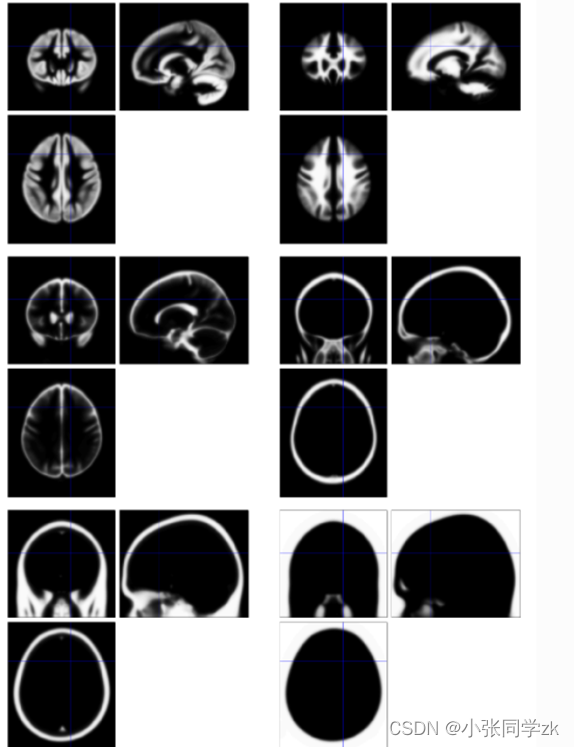

2.1 观察结构像和功能像

按照下图,点击Display,同样功能像也可以这样加进去,我们还可以看每个被试的时间序列信息

观察功能像: